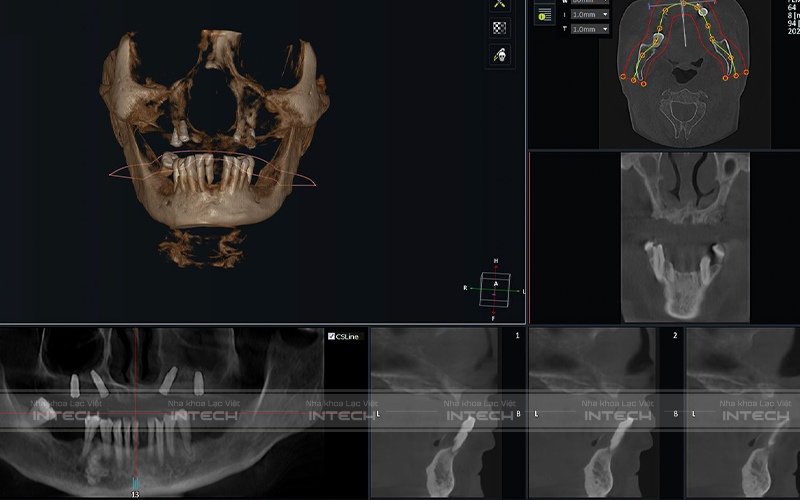

Dựa trên kết quả phim chụp và kiểm tra tổng quát, bác sĩ tại Nha khoa Lạc Việt Intech đã đánh giá, phân tích tình trạng trước của cô Trần Thị Kim Oanh như sau:

• Mất hầu hết các răng hàm trên, các răng còn lại lung lay không giữ được

• Viêm nha chu

• Sử dụng hàm tháo lắp trong một thời gian dài gây tiêu xương nghiêm trọng

• Mất khả năng ăn nhai, sức khỏe suy giảm nghiêm trọng

Qua thăm khám và dựa trên tình trạng răng ban đầu, các bác sĩ tại Lạc Việt Intech đã đưa ra kế hoạch điều trị cụ thể cho Cô Oanh:

• Nhổ bỏ toàn bộ các răng lung lay hàm trên

• Ghép xương vùng răng bị tiêu xương

• Cấy ghép Implant All-On-4 toàn hàm trên

Hình ảnh phim chụp sau cấy ghép Implant của cô Oanh (Ảnh: Nha khoa Lạc Việt Intech)

Với phương pháp điều trị trên kết hợp sử dụng công nghệ độc quyền Safe-Tech, Nha khoa Lạc Việt Intech đã khôi phục răng mất thành công cho cô Trần Thị Kim Oanh.

Việc ứng dụng công nghệ trồng răng Safe-Tech trong quá trình điều trị đã giúp bác sĩ có thể lựa chọn những vị trí xương hàm tốt nhất để đặt chân răng Implant. Đồng thời đảm bảo xuyên suốt hành trình trồng răng Implant diễn ra nhanh chóng, an toàn, không đau, nhanh lành thương nhanh.